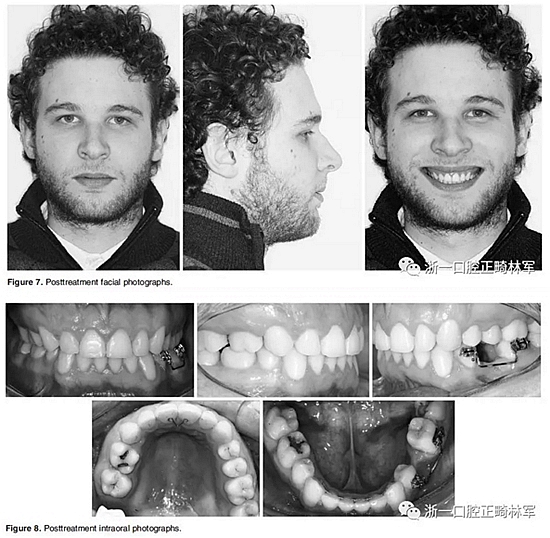

在治療結(jié)束時,面部基本對稱(Figure 7)。上中線與面中線重合,下中線向左偏0.5mm,傾斜的合平面得到矯正,獲得了良好的咬合關(guān)系,具有正常的覆合和覆蓋,留下7mm的空間用于植入左下前磨牙(Figure 8、9)。